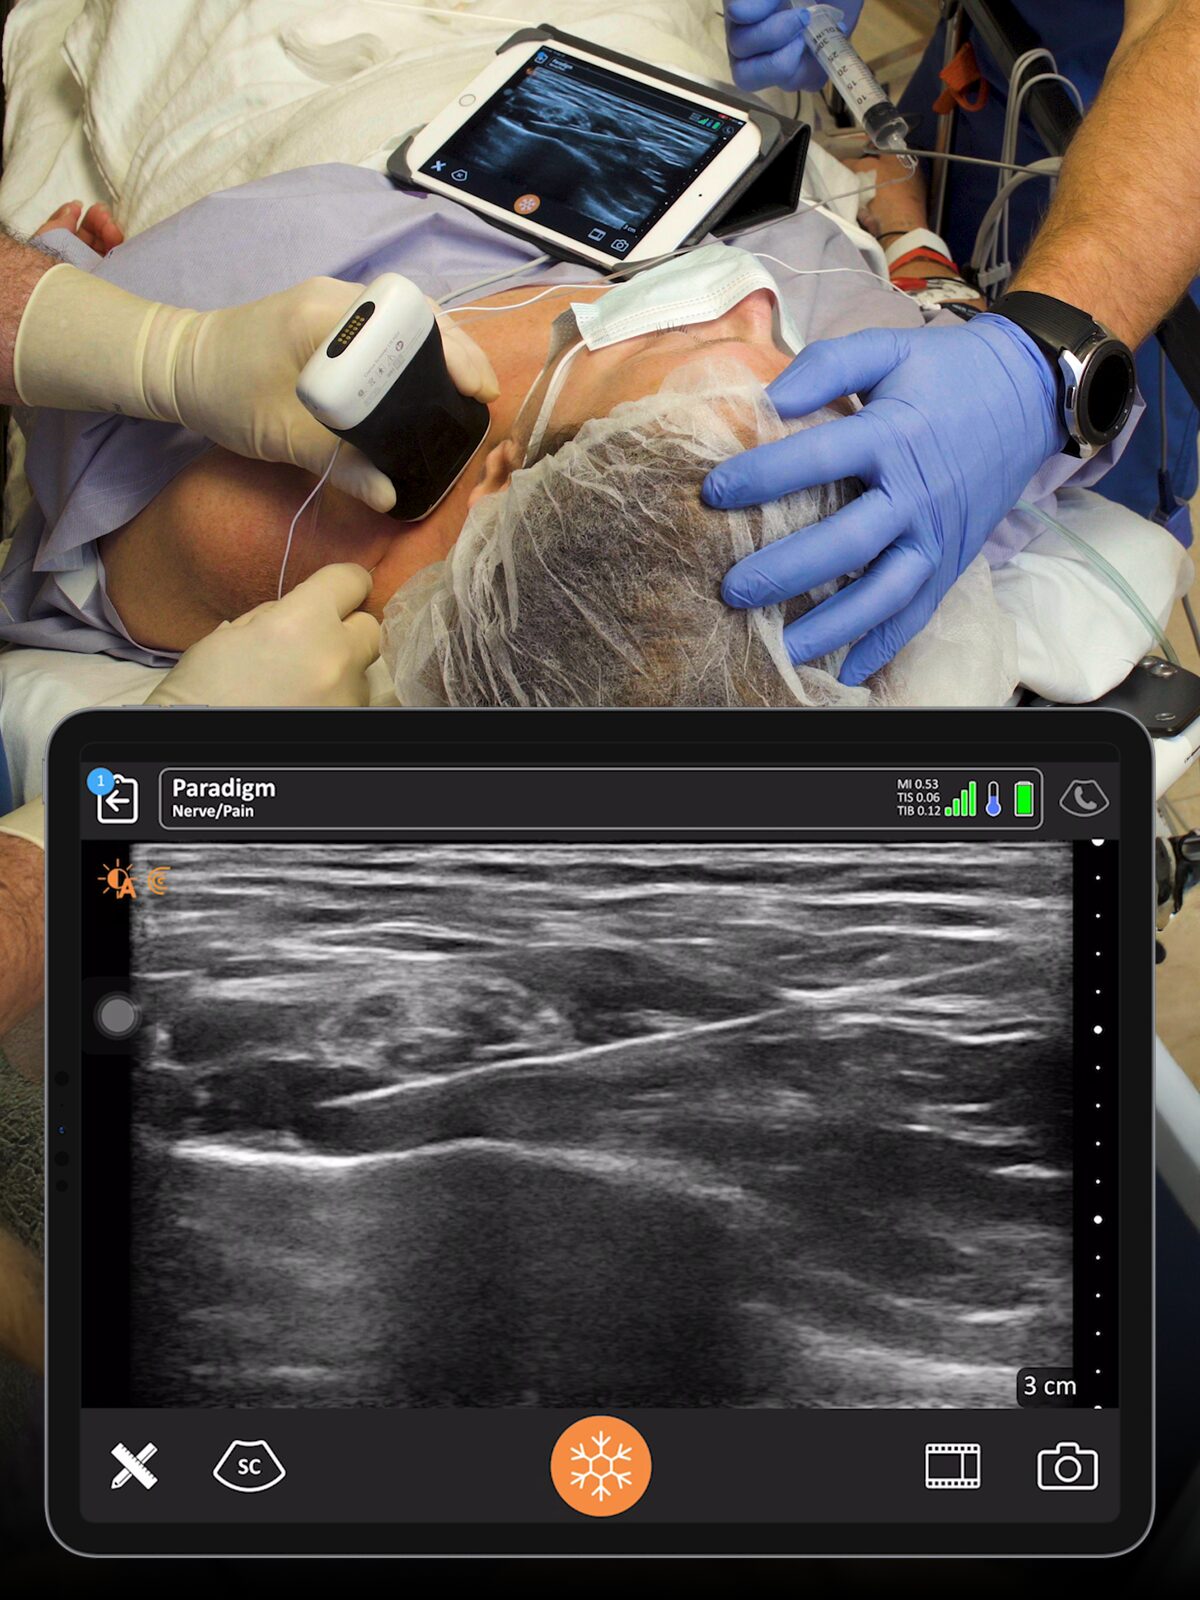

Guide Every Block with Clarity

From pre-op to PACU, guide safe, accurate blocks and pain interventions without disrupting workflow or sterility.